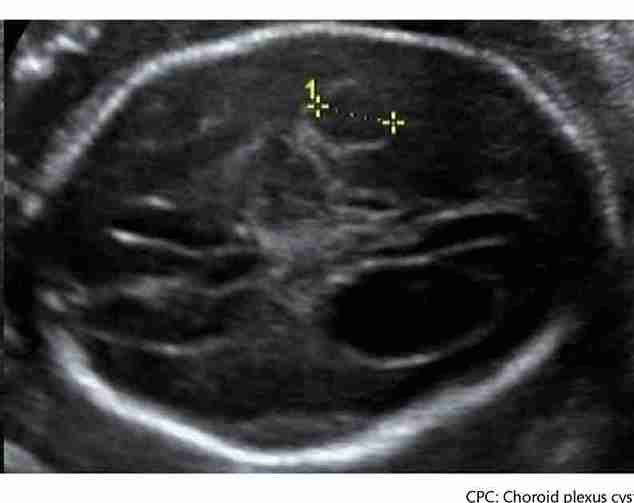

Koroid Pleksus Kisti (KPK), fetal beyinde bulunan ve beyin omurilik sıvısını (BOS) üreten koroid pleksus adı verilen yapının içinde oluşan küçük, sıvı dolu keseciklerdir. Koroid pleksus, gebeliğin erken evrelerinden itibaren aktif olarak çalışan ve beynin normal gelişiminde önemli rol oynayan bir yapıdır. Bu kistler, beyin gelişiminin doğal bir varyasyonu olarak kabul edilir ve genellikle iyi huylu (benign) oluşumlardır.

KPK'ler en sık olarak gebeliğin 18. ila 24. haftaları arasında yapılan ikinci trimester detaylı ultrasonografi (anomali taraması) sırasında tespit edilir.

Deneyimli bir perinatoloji uzmanı, bu muayene sırasında bebeğin beyin yapılarını dikkatlice incelerken koroid pleksus içinde sıvı dolu kesecikleri (kistleri) fark edebilir.

Kistler genellikle tek veya çift taraflı olabilir. Boyutları ve sayıları da ultrasonografi ile değerlendirilir.